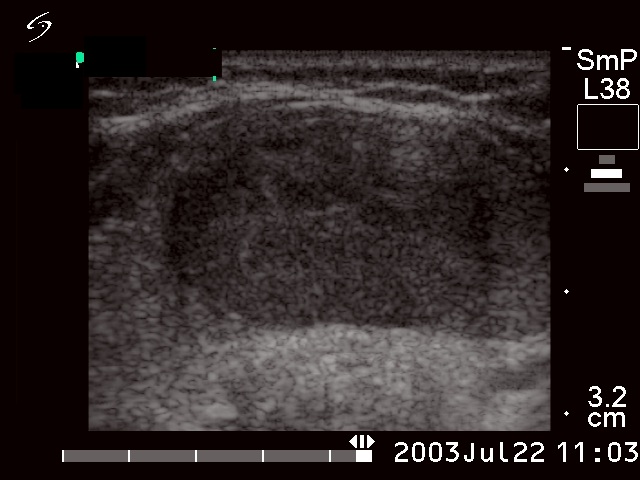

Ultrasonography: the thyroids were already echonormal. (On the first visit a diffuse hypoechogenicity was found.) A hypoechogenic nodule with increased intranodular vascularization was detected in the isthmus.